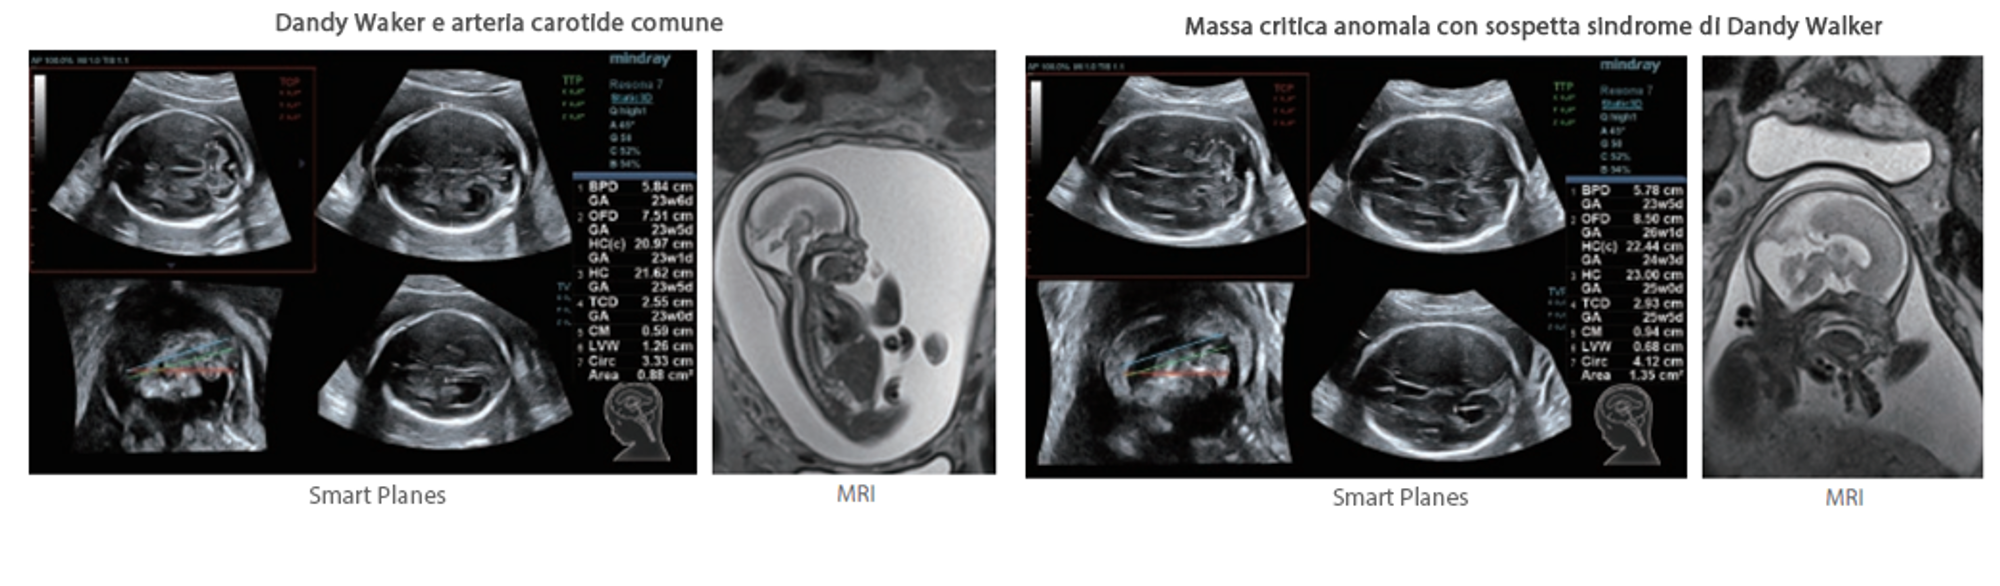

Oltre alla qualit├Ā delle immagini di livello eccellente, Resona 7 migliora anche le capacit├Ā di ricerca clinica il rivoluzionario V Flow per la valutazione emodinamica vascolare, e l'acquisizione piani pi├╣ intelligente dal set di dati 3D per la diagnosi del sistema nervoso centrale fetale. Combinando il pi├╣ intuitivo funzionamento multi-touch basato su gesti e tutte le caratteristiche cliniche essenziali, Resona 7 sta veramente portando nuove tendenze nellŌĆÖinnovazione dellŌĆÖecografia.